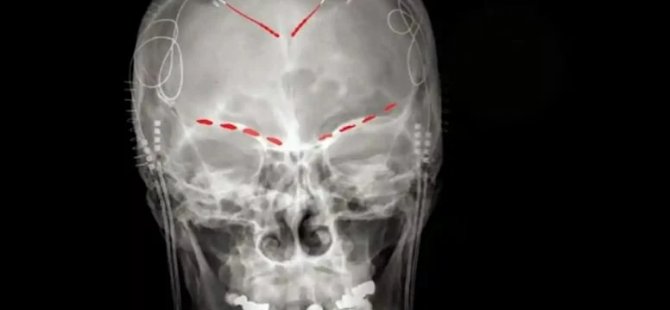

Nature Neuroscience’da yayınlanan son çalışma için Kaliforniya Üniversitesi’nde bir nörolog ve projede baş araştırmacı olan Prasad Shirvalkar ve meslektaşları, inme veya bir uzuv kaybından sonra inatçı kronik ağrısı olan dört hastayla çalıştılar.

Shirvalkar ve ekibi, elde ettikleri verilerde elektrik sinyallerine dayanarak bir kişinin ağrısını tahmin etmek için bir algoritma geliştirdiklerini açıkladı.

Shirvalkar, “Kronik ağrı, akut ağrının sadece daha kalıcı bir versiyonu değil, beyinde temelde farklıdır. Bunu daha iyi anladığımıza göre, bilgiyi en şiddetli ağrı türleri için kişiselleştirilmiş beyin stimülasyon terapileri geliştirmek için kullanabileceğimizi umuyoruz.” dedi.